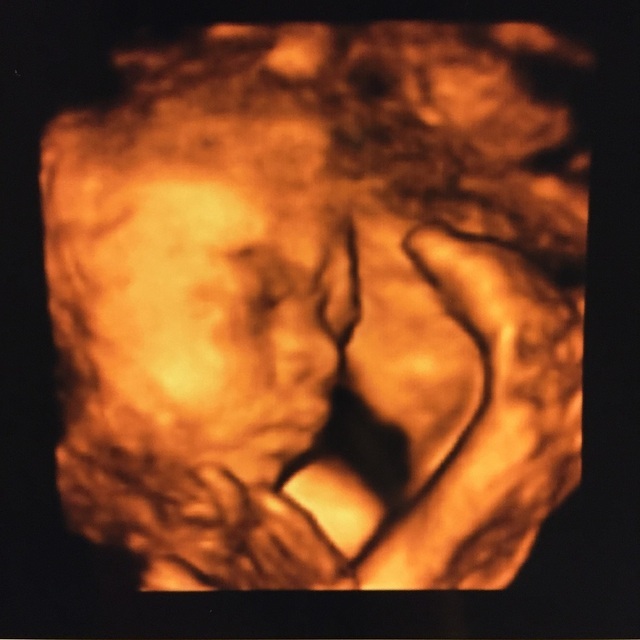

29週0日(29w0d・男の子)|yuiiing52 さん(31歳)

エコー写真撮影時のエピソード:

エコー写真はいつ見ても、どれが顔なのかどれが足とか全然分かりませんでした。3Dと4Dを同じに日に撮って、4Dの方が分かりにくくて、旦那様は全く分かってなくて、帰って録画したのを見て説明しました。

この3Dが1番きれいに撮れて、でも先生はボッコボコとエコーのやつでグイグイ押してたので、こんな押して大丈夫と不安でしたが、いい写真が撮れました。